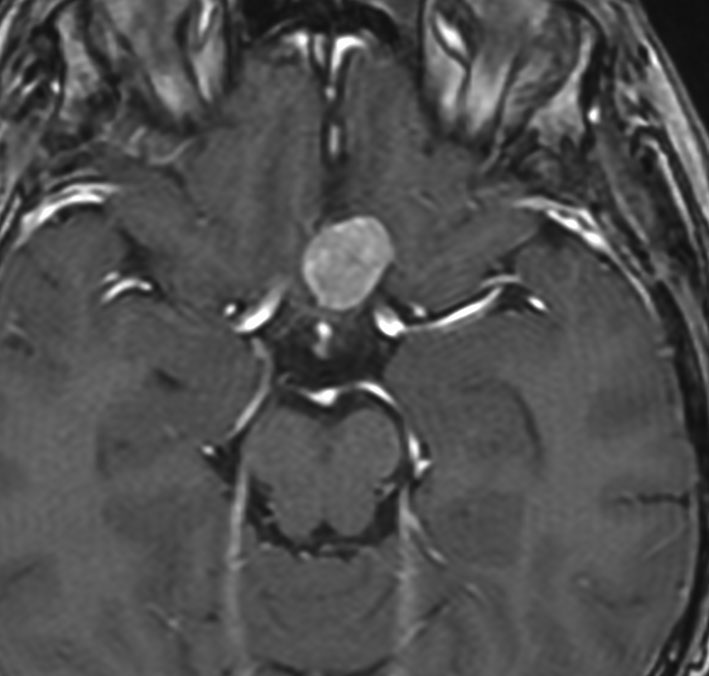

放射線誘発膠芽腫(グリオブラストーマ)

松果体のジャーミノーマのために,19歳の時に全脳照射30グレイと松果体局所照射20グレイを受けました。これは28歳の時に発生した右側頭葉の膠芽腫です。この部分には30グレイしか入っていないのですが,2.5グレイという大きな1日線量が用いられていました。またslit-beam rotationという1990年代初頭に用いられた照射方がされています。同じ線量であっても二次ガンを招きやすい照射法というのがあるのかもしれません。